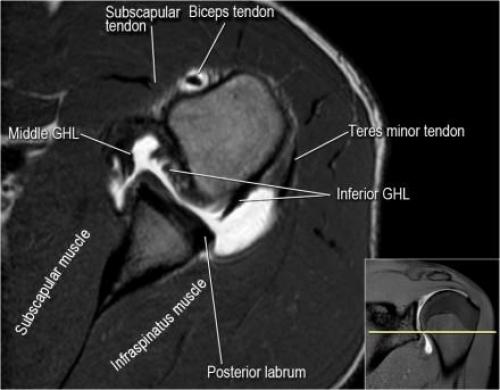

- вогнутость заднебокового края головки плечевой кости не следует путать с повреждением Хилл-Сакса, поскольку это нормальная форма для данного уровня. Повреждение Хилл-Сакса визуализируется только на уровне клювовидного отростка. В предних отделах мы сейчас на урвоне 3-6 часов. Здесь визуализируются повреждение Банкарта и его варианты.

- обратите внимание на волокна нижней плече-лопаточной связки. На данном уровне так же ищется повреждение Банкарта.